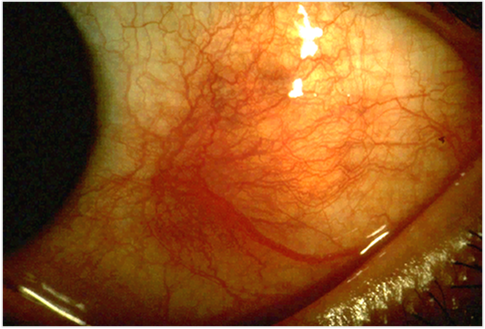

| 미만형(Diffuse) | 가장 흔함, 광범위 충혈, 양호한 예후 |

핵심 소견

- 보라색/파란색 변색: 심부 공막 혈관 확장

- Phenylephrine test: 충혈 지속 (상공막염은 소실)